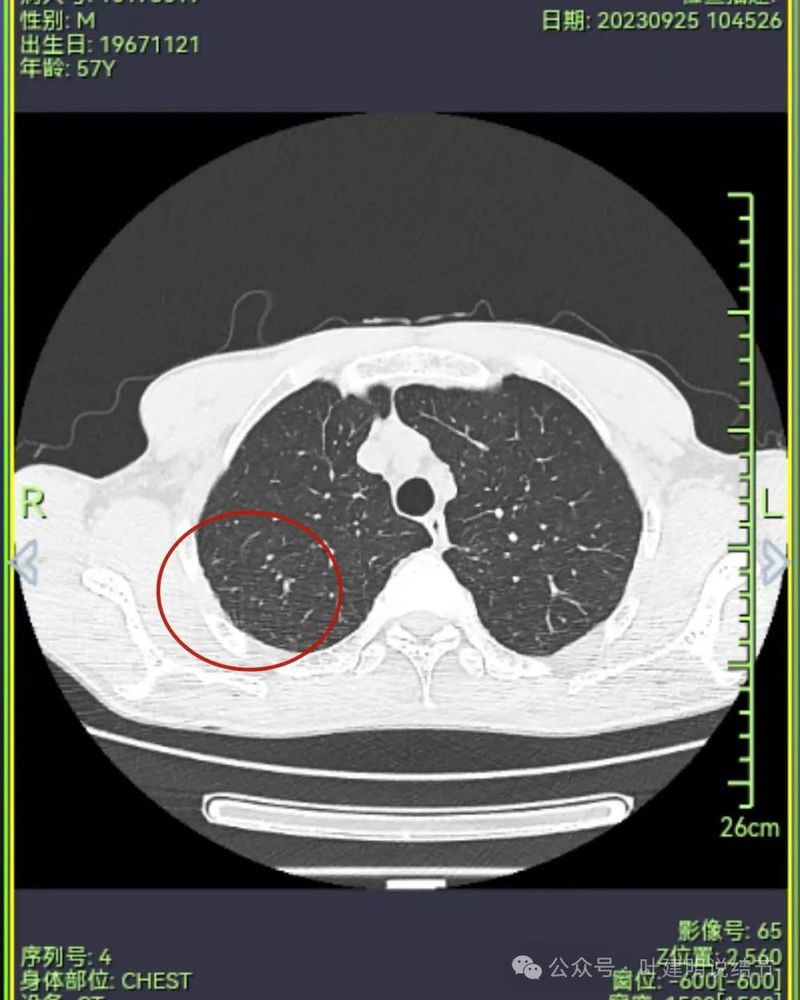

到2023年9月病灶较前进展,或许测量大小变化不明显,但实性成分明显多起来,内部不太致密的部分明显显得较之前密了。

到了2024年5月,病灶整体给人感觉有收缩力了些,内部也更显致密了。

病灶1于2023年9月时都没有的,更说明是炎症性的。